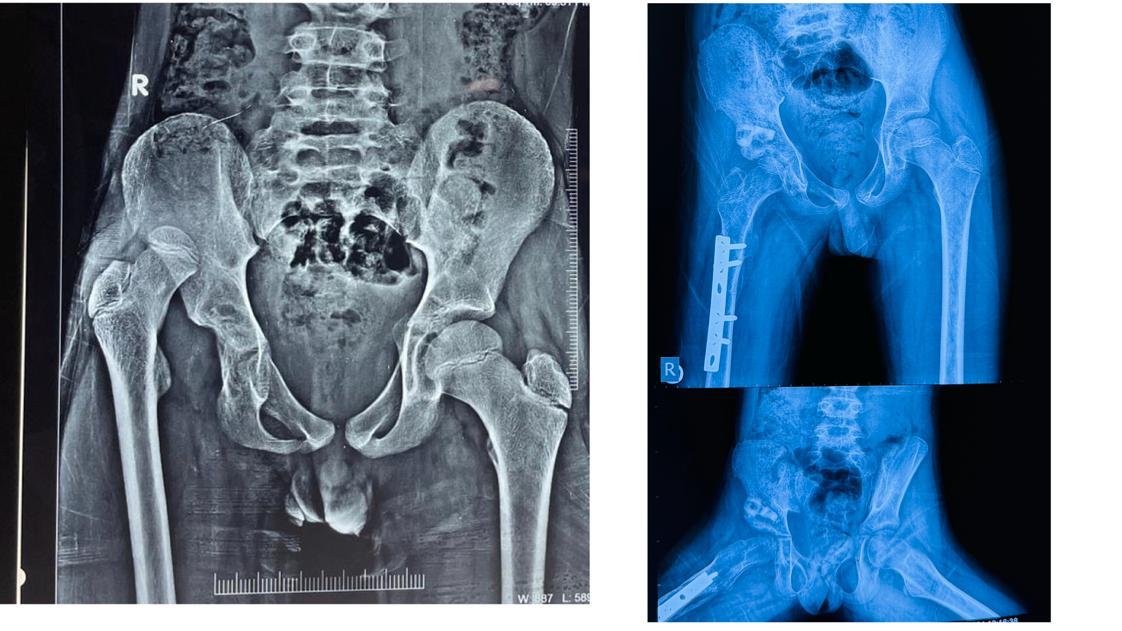

Under the leadership of Dr. Amit Agrawal, a Child Bone Disease Department and Super Specialty Clinic, along with a dedicated Child Orthopedic Unit, has been established at Vishesh Jupiter Hospital. This unit is specially designed to provide expert and specialized orthopedic care for children, ensuring accurate treatment and better recovery outcomes.